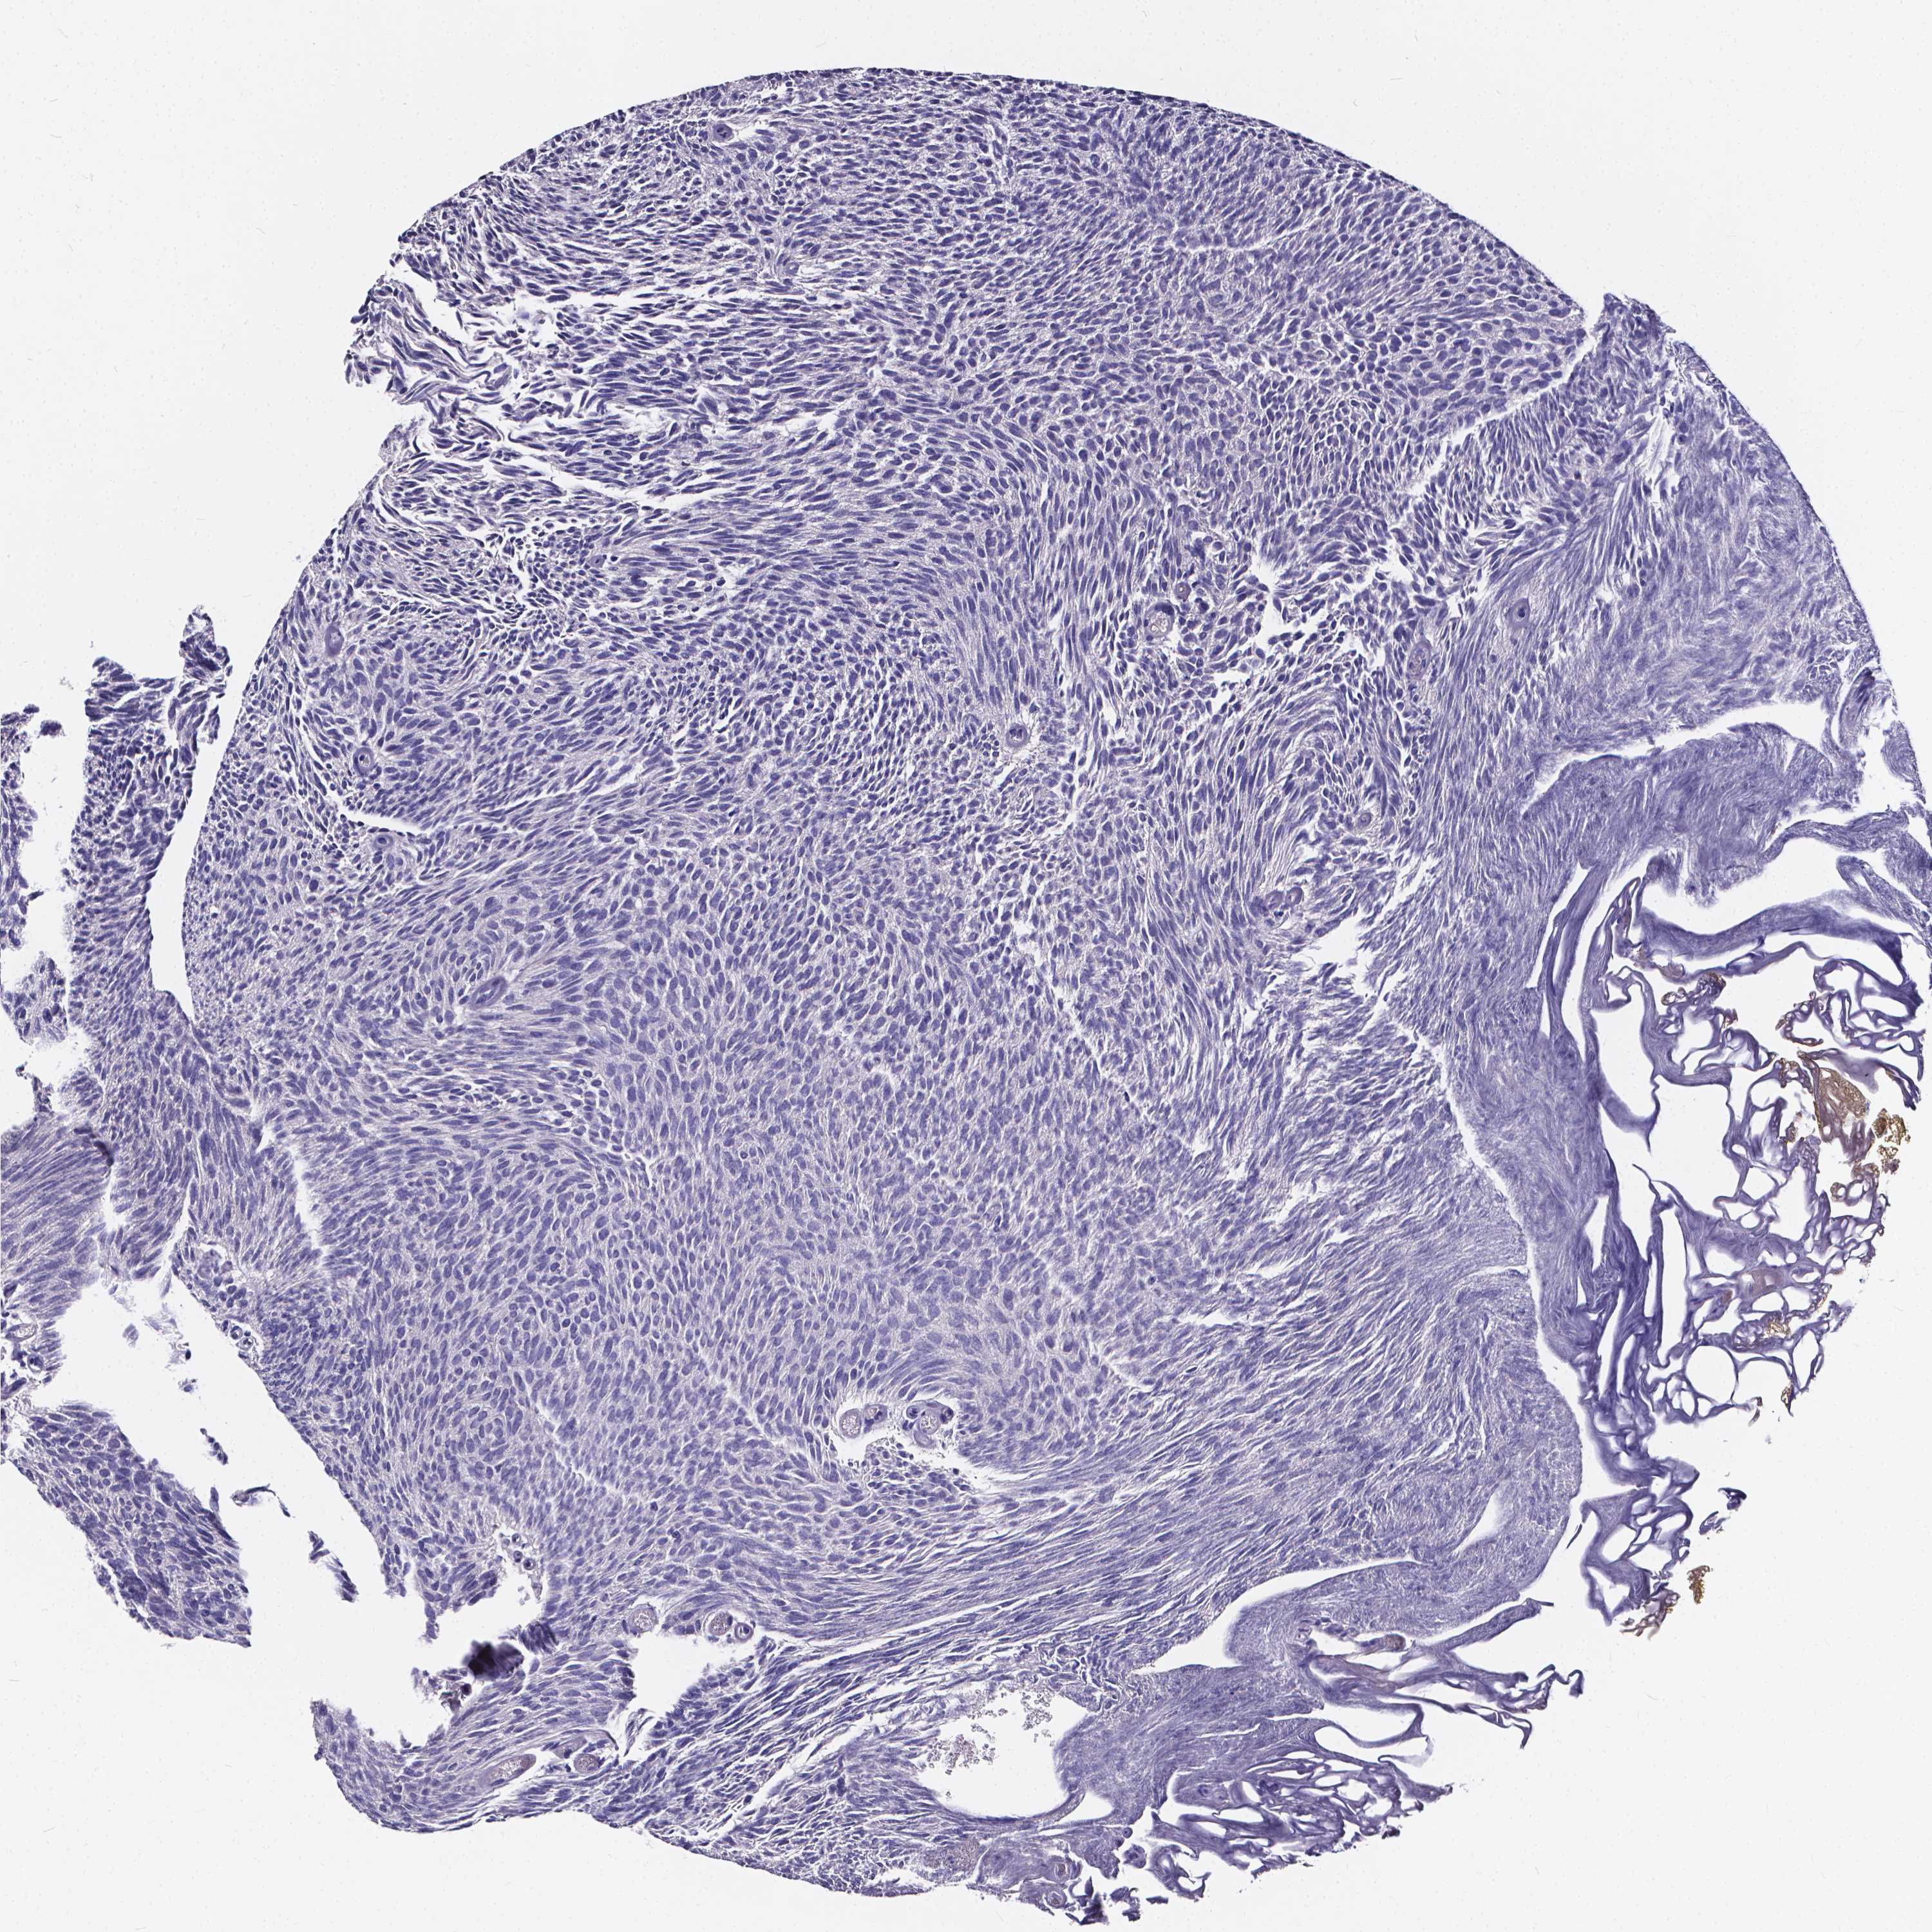

UROTHELIAL CANCER - Protein expressioni

A mouse-over function shows sample information and annotation data. Click on an image to view it in a full screen mode. Samples can be filtered based on level of antibody staining by selecting one or several of the following categories: high, medium, low and not detected. The assay and annotation is described here.

Note that samples used for immunohistochemistry by the Human Protein Atlas do not correspond to samples in the TCGA dataset.

Antibody stainingi

Antibody staining in the annotated cell types in the current human tissue is reported as not detected, low, medium, or high, based on conventional immunohistochemistry profiling in selected tissues. This score is based on the combination of the staining intensity and fraction of stained cells.

Each image is clickable and will lead to virtual microscopy that enables deeper exploration of all samples and also displays staining intensity scores, fraction scores and subcellular localization as well as patient and tissue information for each sample.

Antibody HPA064621

Staining

High

Medium

Low

Not detected

Intensity

Strong

Moderate

Weak

Negative

Quantity

>75%

75%-25%

<25%

None

Location

Nuclear

Cytoplasmic/membranous

Cytoplasmic/membranous,nuclear

Urothelial carcinoma, High grade

Urothelial carcinoma, NOS

Urothelial carcinoma, Low grade